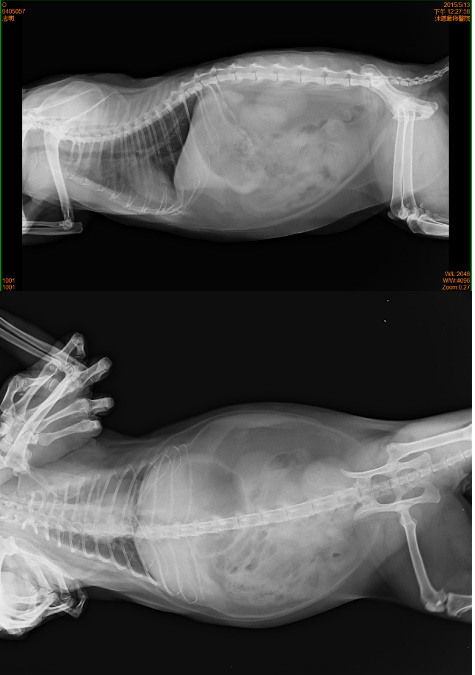

主題: 膀胱發炎的志明 申請者姓名: 臺北市支持流浪貓絕育計劃協會 花色: 申請日期: 2015-07-08 16:12:47 申請者部落格: 申請者臉書網址: 所在縣市/合作醫院: 台北市/沐恩動物醫院 治療費用: 7230元 需求人數: 8人 已結案 (2022-05-13 15:06:04) 報名人員: Bonnie Lee(已付款)、Cherry Huang(已付款)、洪家寶(已付款)、小米(已付款)、Shirley Chen(已付款)、Shirley Chen(已付款)、Erin Yang(已付款)、Chris Chen(已付款)、 候補人員: 動物病情說明: 志明

志明已經變得白白胖胖肥肥嫩嫩,有6.8公斤的巨大體型,雖然他的雙腳斷肢因為摩擦有厚厚的繭,在室內還是鋪了厚紙板讓志明行走更加舒服,2015/3月起照顧員發現志明排尿似乎有點困難在砂盆裡蹲很久,送醫檢查,採尿送檢,尿中有草酸鈣結晶,醫生建議要吃泌尿道處方,並給予利尿通幫助,經過兩個月狀況反反覆覆,5/13再次進行超音波檢查,發現膀胱依舊有很多雜質陰影變大,肝指數較高,X光上沒有明顯結石,抽尿液送驗,先給予口服抗生素和膀胱鬆弛劑並每天打水希望藉此將雜質隨尿液排出,還需持續回診,這階段的醫療費用還請各位幫忙。